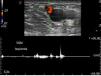

La exploración comienza en la arcada inguinal, con un corte transversal a la altura de la unión safeno-femoral (signo de Mickey Mouse) (fig. 2). Se evalúa el reflujo a ese nivel (el de la vena femoral común, la vena femoral y la VSM [figs. 3 y 4]) mediante maniobras de Valsalva con Doppler color y espectral (fig. 5).